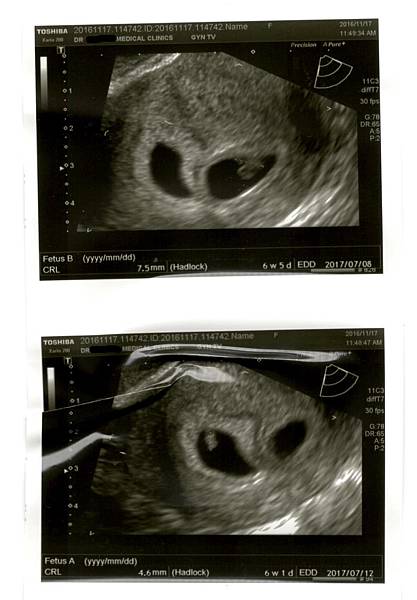

確認是「雙胞胎」!懷孕4周至9周的產檢(超音波及抽血報告)

過去一個月都很忙很累(忙著做各類的檢查),身體的不適感也越來越嚴重,所以一直提不起勁仔細紀錄最近的狀況。